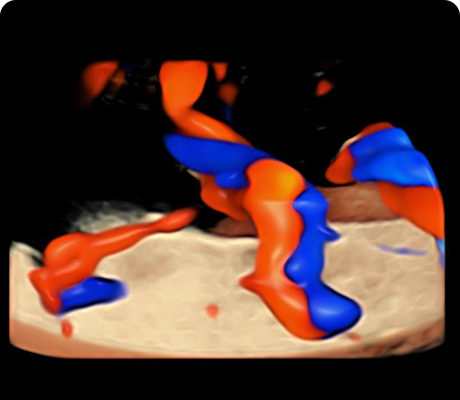

En la Clínica de Medicina Materno Fetal del Hospital Angeles Lomas, ofrecemos detección oportuna de enfermedades en el feto y complicaciones en la madre, mediante estudios de genética e imagen con tecnología avanzada y médicos altamente especializados.

"Durante el embarazo, los ultrasonidos son una parte fundamental del control prenatal. Nos permiten observar el desarrollo del bebé, identificar posibles complicaciones a tiempo y tomar decisiones médicas informadas para cuidar tu salud y la de tu bebé."